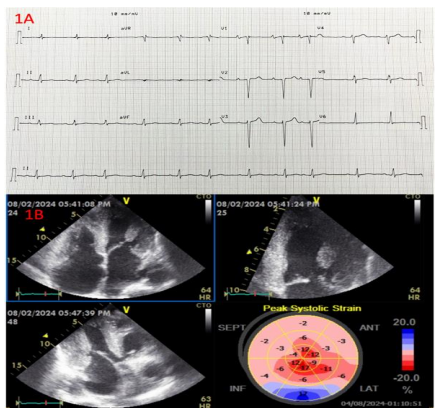

Figures 1A and 2A show two ECGs of patients with diagnosis AL and ATTRwt cardiomyopathies and the typical ECG findings.

Figures 2A. ECG performed to a 59-year-old patient male with monoclonal gammopathy of unknown significance (MGUS) and ATTRwt amyloid cardiomyopathy what depicts sinus rhythm, low QRS voltage in the horizontal plane, pseudo-infarction pattern in precordial leads with non-specific T wave abnormalities in I-aVL and inferior leads and T wave inversion in V6 lead, left atrial enlargement signs and poor R wave progression in precordial leads. 2B. Echocardiographic apical 4 chambers, apical three chambers, apical 2 chambers views with the 2D GLS Bull’s eye display depicting idem findings like figure 1B.

Echocardiography is cost-effective, readily available, bedside to perform, and an excellent tool to identify systo-diastolic dysfunction. Although not always present, classic echocardiography findings of infiltrative disease include left ventricle wall thickening, small left ventricle cavity size, biatrial enlargement, thickened valves, elevated right ventricular systolic pressure and atrial septum thickness, granular sparkling appearance of the myocardial wall, pericardial effusion, restrictive transmitral Doppler filling pattern, and reduced ventricular strain, apical-to-basal strain ratio >2.1, left ventricle ejection fraction-to-strain ratio >439-41. (Table 1; Figure 1B and 2B).

Reduction in global longitudinal strain (a measure of systolic function) is one of the earliest markers of cardiac amyloidosis and presents with a characteristic pattern of relative apical sparing of longitudinal strain (ie, the ratio of apical longitudinal strain/average of mid and basal longitudinal strain >1.0)41. This pattern of longitudinal strain alteration has high sensitivity (93 percent) and specificity (82 percent) for cardiac amyloidosis with proven utility in differentiating cardiac amyloidosis from other hypertrophic phenocopies41,42.